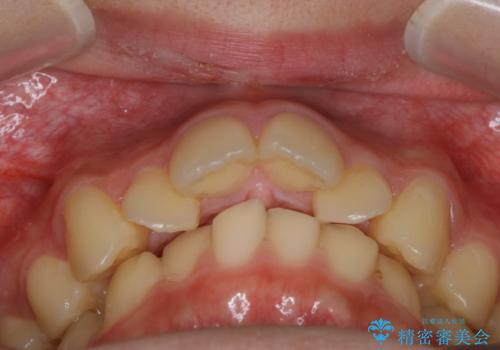

非抜歯で劇的に出っ歯を改善!インビザラインとカリエールの組み合わせ治療

- 患者様、出っ歯のお悩みで来院されました。

骨格の分析を行ったところ上顎も出てはいるのですが、下顎が引っ込んでいる状態であるということがわかりました。

よって上顎の歯を抜いて治療をするのではなく、カリエールという器具を使用して下顎を前に引っ張り出しながら上顎を引っ込めるという治療を行うことにしました。

ひと口に出っ歯(上顎前突)といっても原因は多様です。

骨格的な問題があるのか、歯だけの問題なのか、上顎が出ているのか、下顎が出ているのか。あるいはその両方か。

きちんと原因を見極めたうえで治療を開始しないと仕上がりは理想的になりません。

矯正検査を行い、しっかりと矯正診断を行った上で治療を開始することが大事です。